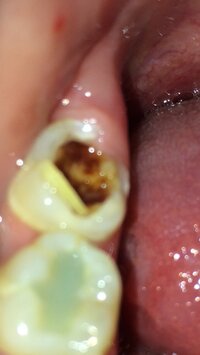

虫歯になると、歯のエナメル質が失われて、歯がスカスカになりもろくなっていく。 Photo・イラスト:Rocketnews24 超斬新だけど怖い歯のデザインをネイルデコにしたサロン むし歯のイラスト 汚れた歯の上に立って、虫歯菌が笑っているイラストです。 公開日: スポンサード リンク スポンサード リンク カテゴリー: 医療, 歯, 人体, 病気 いらすとやに掲載されているイラストは、無料でご利用いただけますが著作権は放棄しておりません。 ご利用イラ 虫歯 イラスト かわいい 虫歯 イラスト かわいい虫歯菌のイラスト素材 虫歯と虫歯菌キャラクターの歯科イラスト素材です カテゴリ 歯科虫歯 商品id 2640 56 31 イラストを探す 季節 春3月4月5月 夏6月7月8月 秋9月10月11月 冬12月1月2「歯 虫歯菌 ばい菌 かわいい

お口の中にはたくさんの細菌が住んでおり、その中のひとつ ストレプトコッカスミュータンスレンサ球菌がおもな虫歯の原因菌です。 お口の中の虫歯菌が、食べ物の中の 砂糖 を栄養に、歯の表面に ネバネバした物質 をつくります。 その ネバネバした物質 の中に 虫歯菌や他の細菌が歯